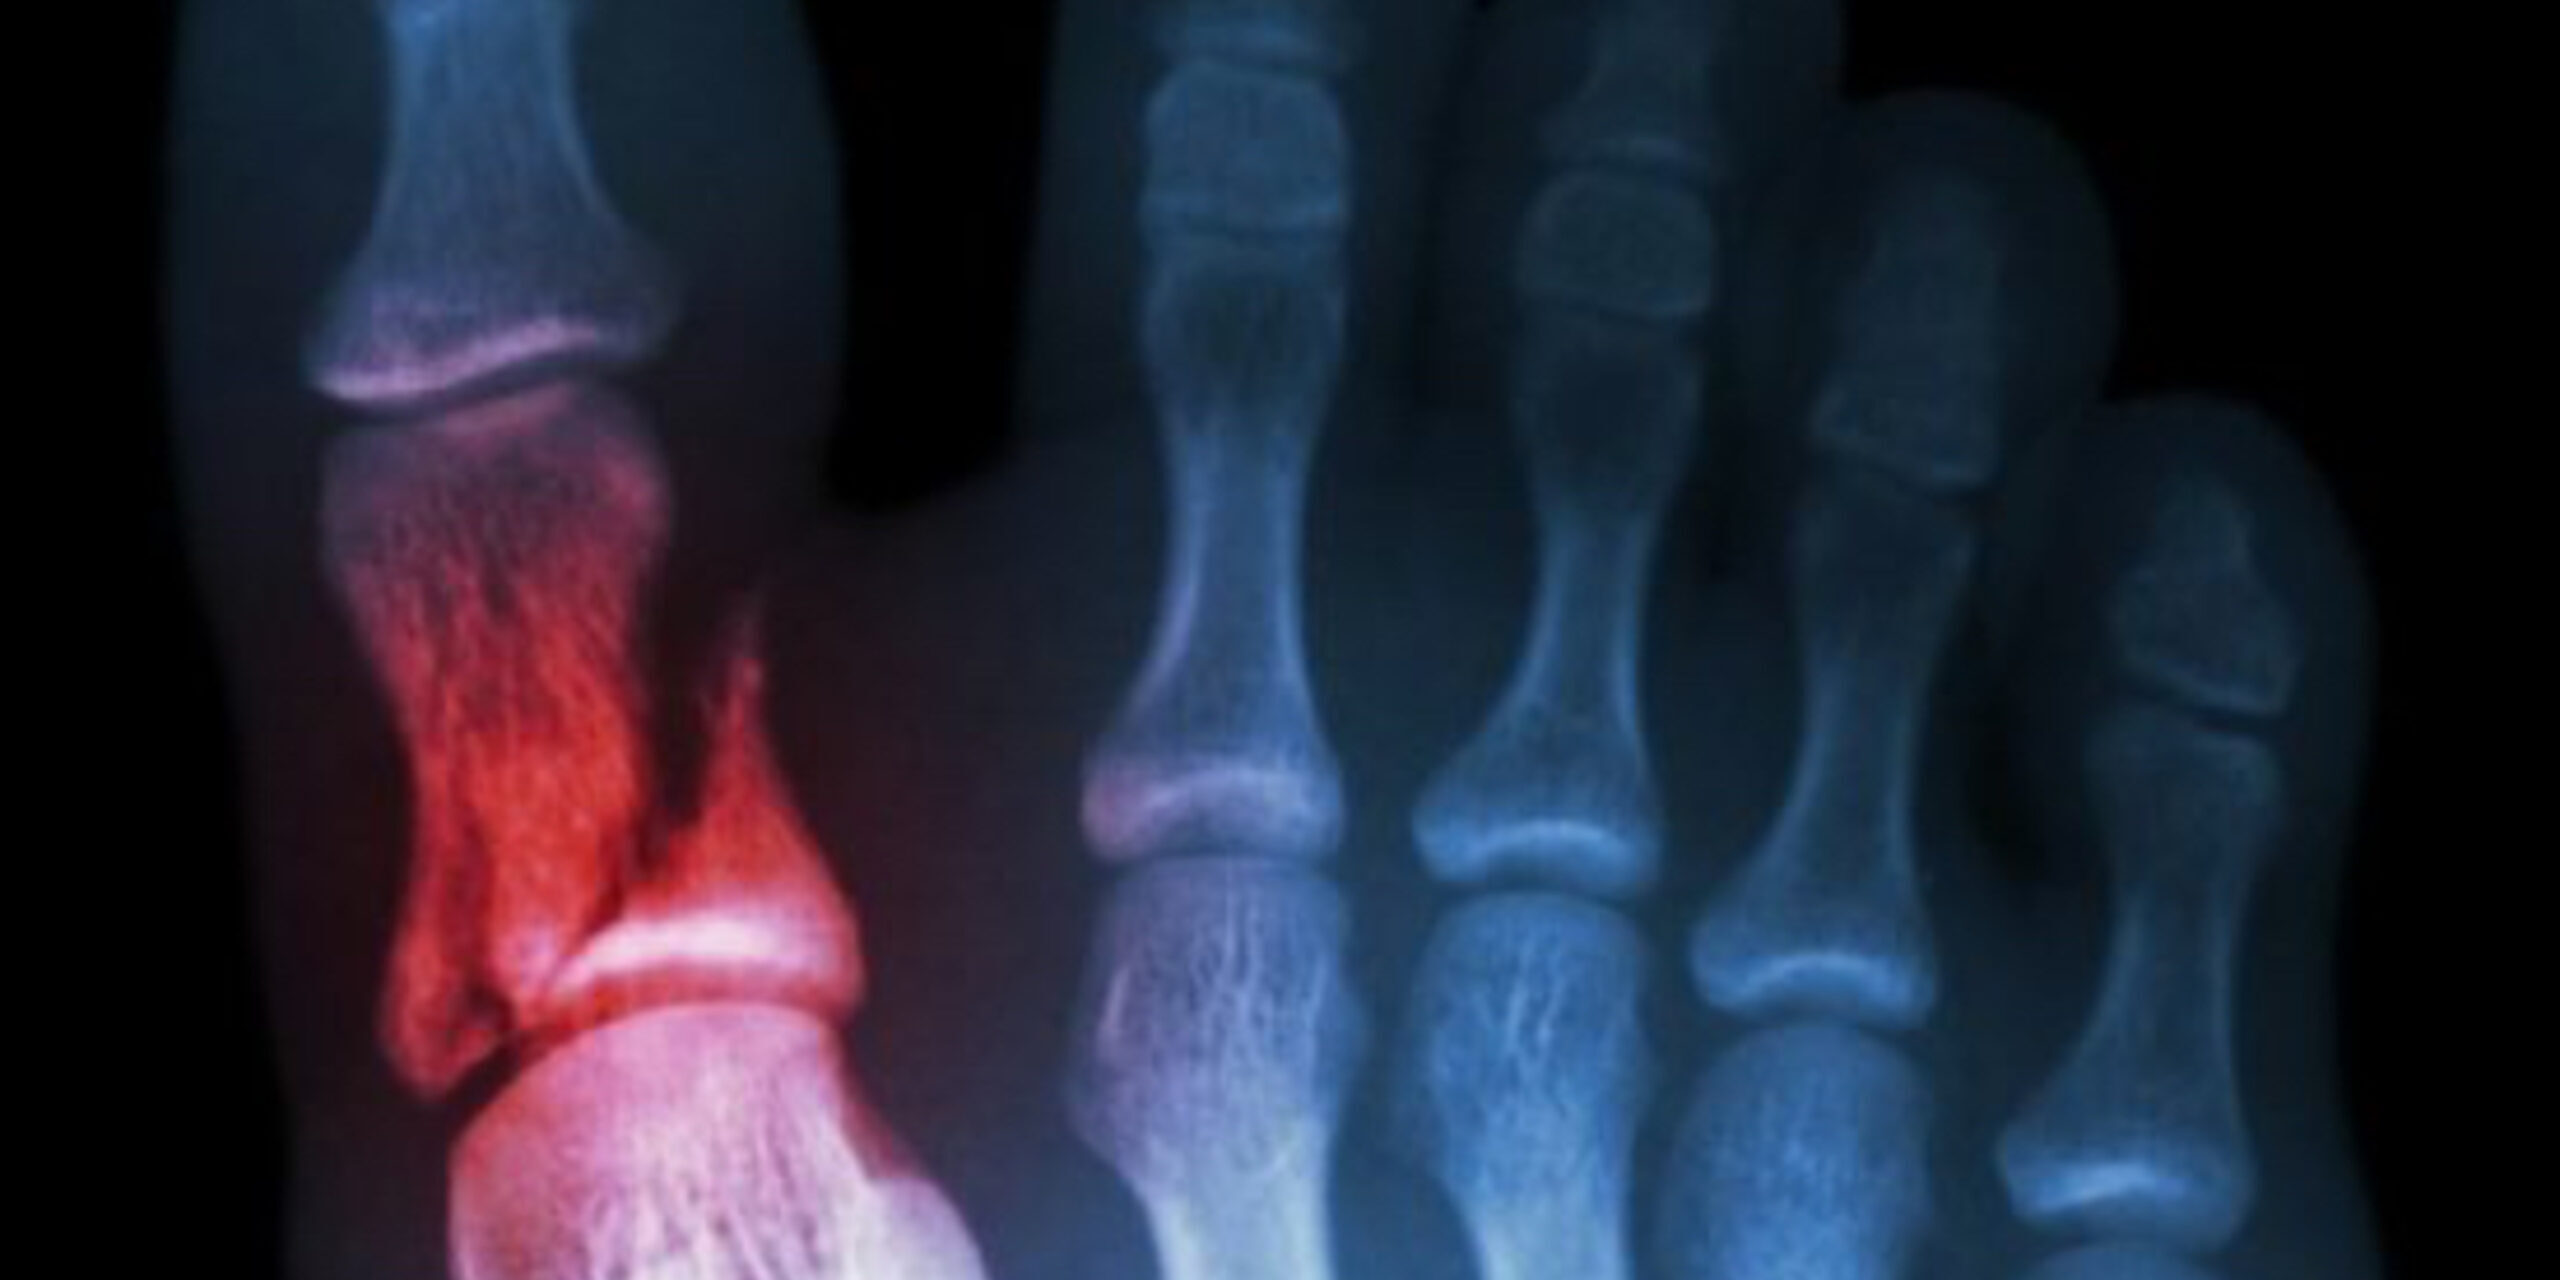

Does God really care about the small things—like your big toe? In this episode, we explore how God’s attention to detail reveals His deep love for us. From a word of knowledge about a toe injury to a powerful encounter of surrender and healing, discover how giving God your hurts can lead to freedom.